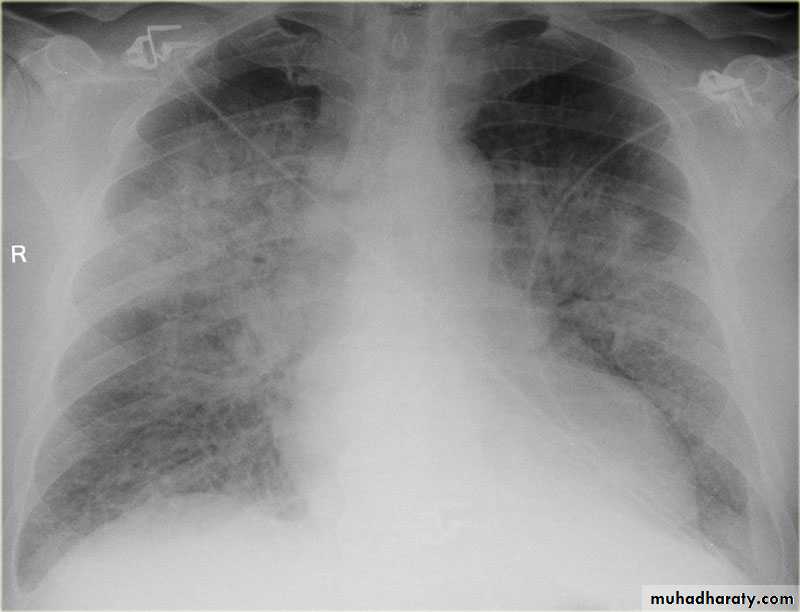

Radiographic featuresPlain film

Typical radiographic features of mitral regurgitation include :

frontal projection

1.left atrial enlargement

convexity or straightening of the left atrial appendage just below the main pulmonary artery (along left heart border)

2.double density sign: the right side of the enlarged left atrium pushes into the adjacent lung and creates an addition contour superimposed over the right heart

3.elevation of the left main bronchus and splaying of the carina

4.upper zone venous enlargement due to pulmonary venous hypertension

5.left ventricular enlargement is also eventually present due to volume overload

6.Features of pulmonary oedema may also be present.

Mitral valve disease